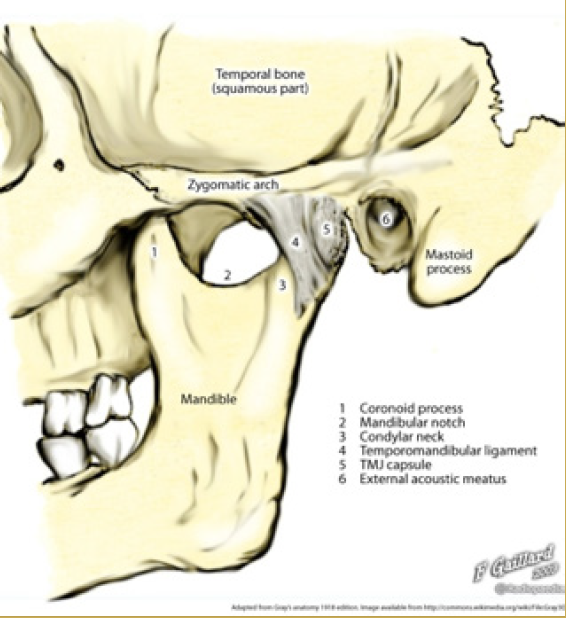

Fractures of the facial bones present an even more complex problem. The most frequent site of bony injury is the zygoma (cheekbone). Fractures of the zygoma account for approximately 10% of the maxillofacial fractures seen in sports injuries, occurring as a result of direct blunt trauma from a fall, elbow, or fist.12 In a study by Linn and others, of the 319 patients treated for sports-related injuries, males proved to be more prone to zygomatic fractures than females because of the powerful physical contacts during sports.13 Like the zygoma, the prominent shape and projection of the mandible cause it to frequently be traumatized. Approximately 10% of maxillofacial fractures from sporting activities occur in the mandible when the athlete strikes a hard surface, another player, or equipment. In a mandibular fracture, airway management is the most important aspect of immediate care.14 In both children and adults, the condyle is the most vulnerable part of the mandible. Fractures in this region have the potential for long-term facial deformity. Recent data suggest that condylar fractures in children can alter growth of the lower face.11

TMJ Injuries

Most blows to the mandible do not result in fractures, yet significant force can be transmitted to the temporomandibular disc and supporting structures that may result in permanent injury (Figure 1 and Figure 2). In both mild and severe trauma, the condyle can be forced posteriorly to the extent that the retrodiscal tissues are compressed. Inflammation and edema can result forcing the mandibular condyle forward and down in acute malocclusion. Occasionally this trauma will cause intracapsular bleeding, which could lead to ankylosis of the joint.

Fig 1. TMJ Landmarks

Figure 1